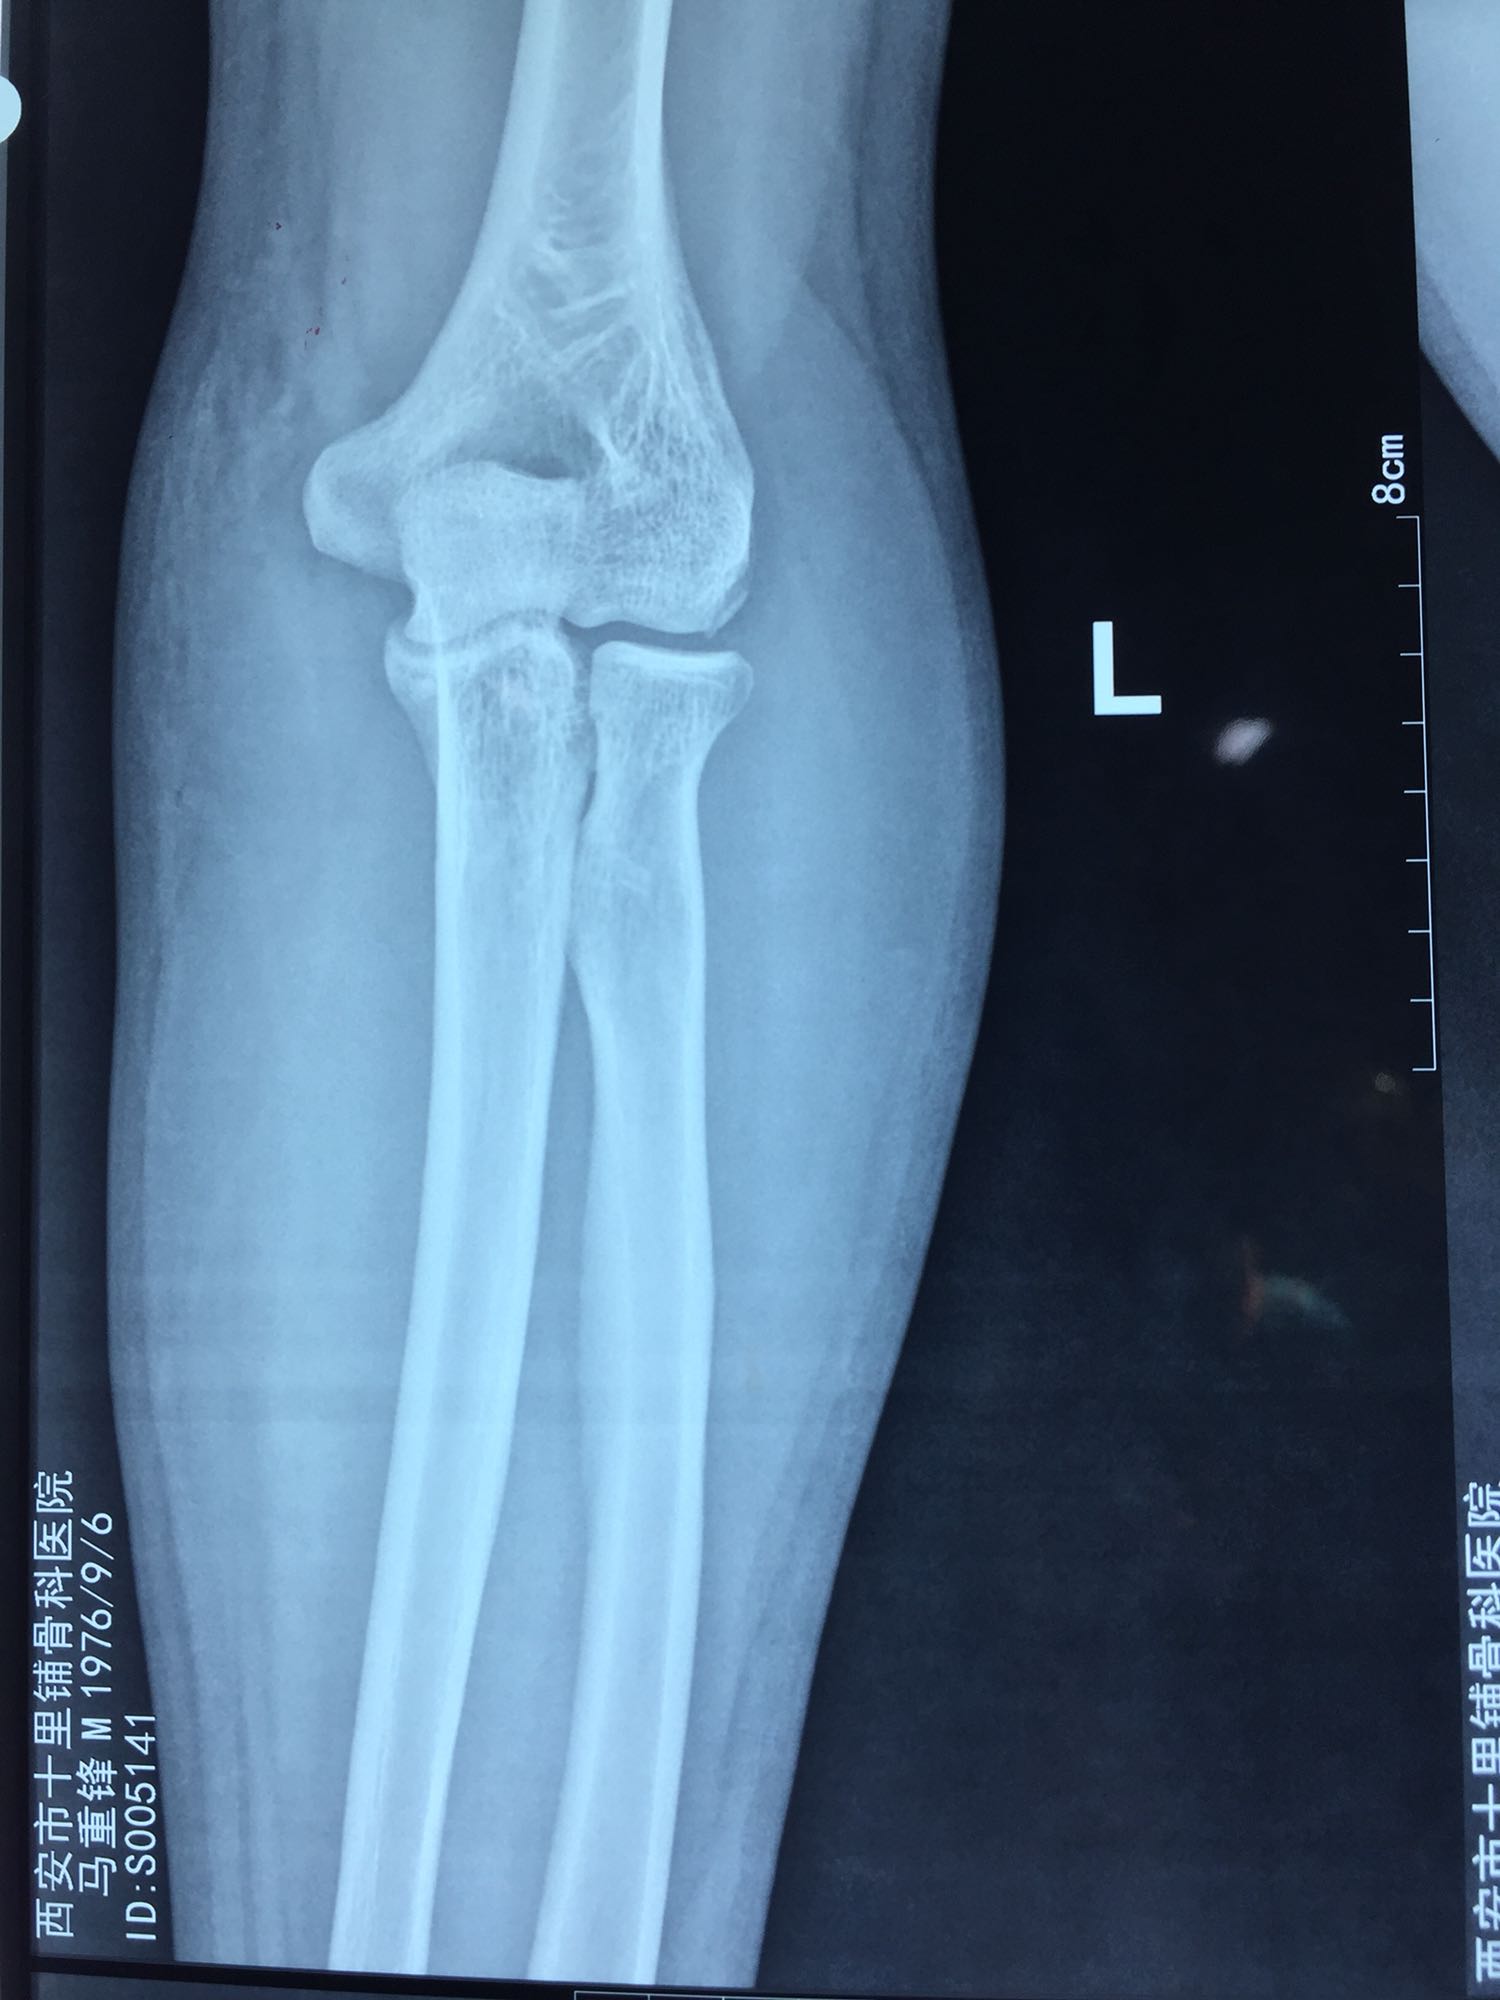

左肘关节高度肿胀,压痛强阳性,肘关节明显活动受限,末梢血运良好,各指关节运动正常。 X线片及CT如图:

1、左尺骨冠状突骨折;2、左肱骨外髁撕脱骨折 治疗:入院后伤肢石膏外固定,给予局部冷敷消肿治疗,于伤后一周行骨折手术治疗,先行前内侧切口复位固定冠状突骨折,活动肘关节发现关节明显不稳定,随取外侧切口,复位固定肱骨外髁,修补外侧副韧带,肘关节明显稳定。术中术后片子如下